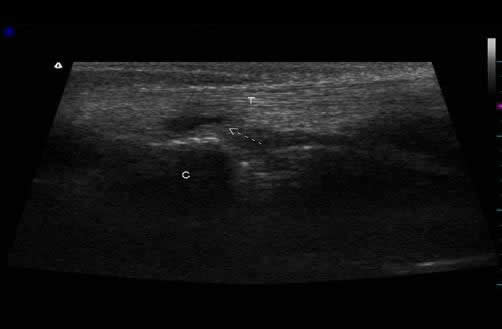

3) Ultrasonografía musculoesquelética previo al alta médica: Fotos 3 A, B. Articulación del codo. (A) Imagen corte longitudinal. No se visualiza bolsa sinovial y tendón del músculo tríceps braquial tiene aspecto fibrilar. (B) imagen de corte transversal aspecto moteado normal.